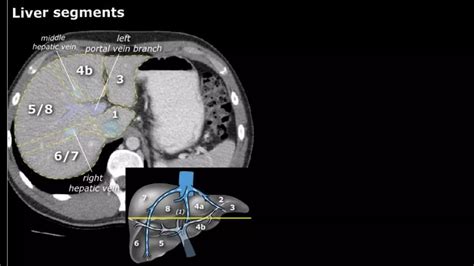

• Pre-surgical planning: Helping surgeons map out the liver's blood vessels and structural anatomy before procedures.